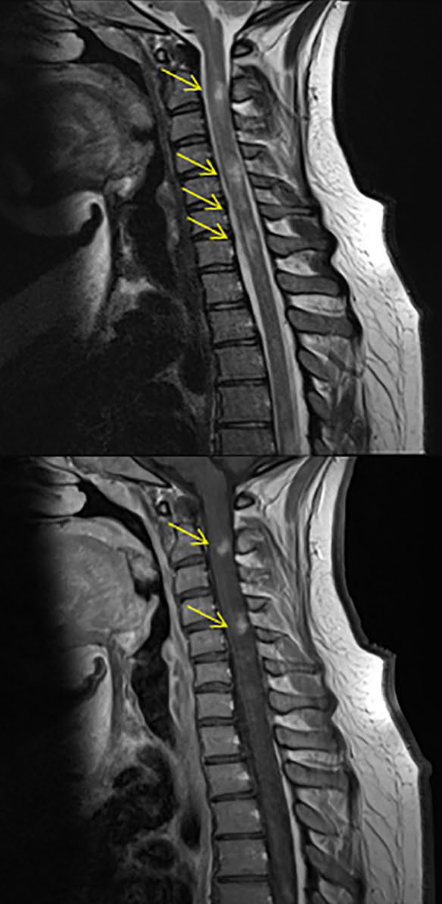

Vírus John Cunningham (JCV)

NATALIZUMABE

LEMP

- 2008 Foi descrito o primeiro caso de LEMP

- 2010-2011 Identificado o tempo de uso da droga e o uso prévio de imunossupressores como fatores de risco

- 2011-2012 Presença do anticorpo Anti-JCV como fator de risco

- 2016-2017 Avaliação do risco mensurada pelo Índice JCV

- 2014-2016 Monitorização por exames de RM mais frequentes

Risco de LEMP monitorizado pelo Índice JCV

Risco de LEMP, Índice JCV e Frequencia de Imagem

- Pacientes com risco de LEMP se beneficiaram da realização mais frequente de RM a cada 3-4 meses

- Foi possivel identificar o aumento de volume, identificar melhor as características e a disseminação